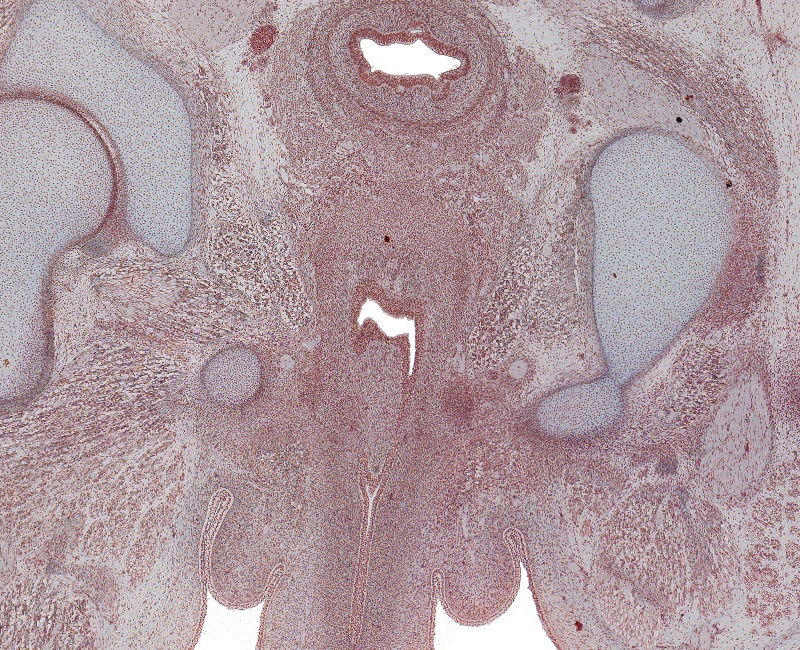

Tissue

Corpus Spongoisus, Urethra in Penis, Rectum, and Fused Paramesenephric Ducts

Carnegie Embryo #9226

198-01-01